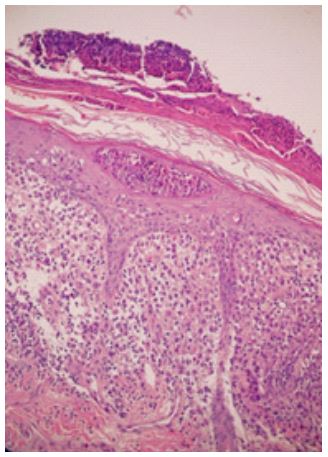

Histopathological findings: A skin biopsy displayed a dense histiocytic infiltrate in the papillary dermis, accompanied by a mixed inflammatory infiltrate and abundant eosinophils (Figure 3). Immunohistochemistry confirmed the presence of CD68, CD1a, S100, and Langerin (CD207), supporting the diagnosis of LCH. Additionally, the BRAFV600E mutation study yielded positive results.

Figure 3: Skin biopsy stained with hematoxylin-eosin, demonstrating a dense cellular infiltrate in the papillary dermis, composed of histiocytes and mixed inflammatory cells.